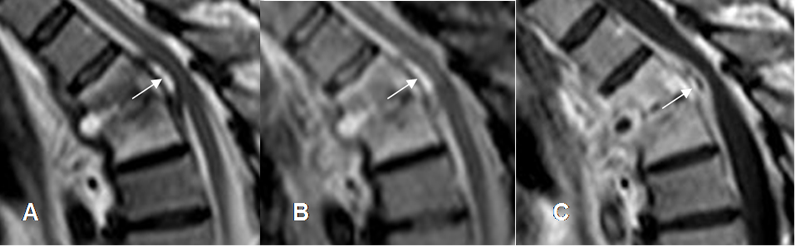

Fig 142. Absceso epidural.

A: RM sagital en T2, B: RM Sagital en STIR y C: RM sagital en T1 con contraste. Pequeña colección hiperintensa en T2 y STIR, con realce heterogéneo del contraste, que comprime anteriormente el saco dural.